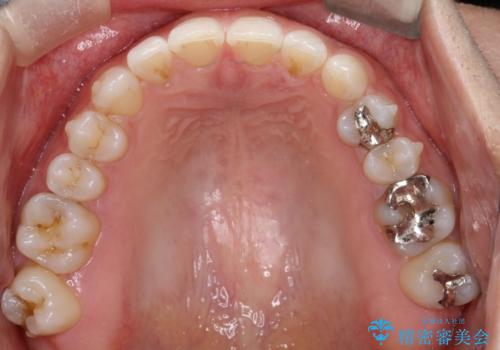

- 前歯の正中離開(すきっ歯)の改善を希望され来院された患者様です。

初診時の歯並びの状態としては、上顎中切歯間に1mm程の隙間があり、その他に見た目に関して気になるような問題点はない状態でした。

インビザライン(マウスピース)にて上顎のみの矯正治療を行いました。